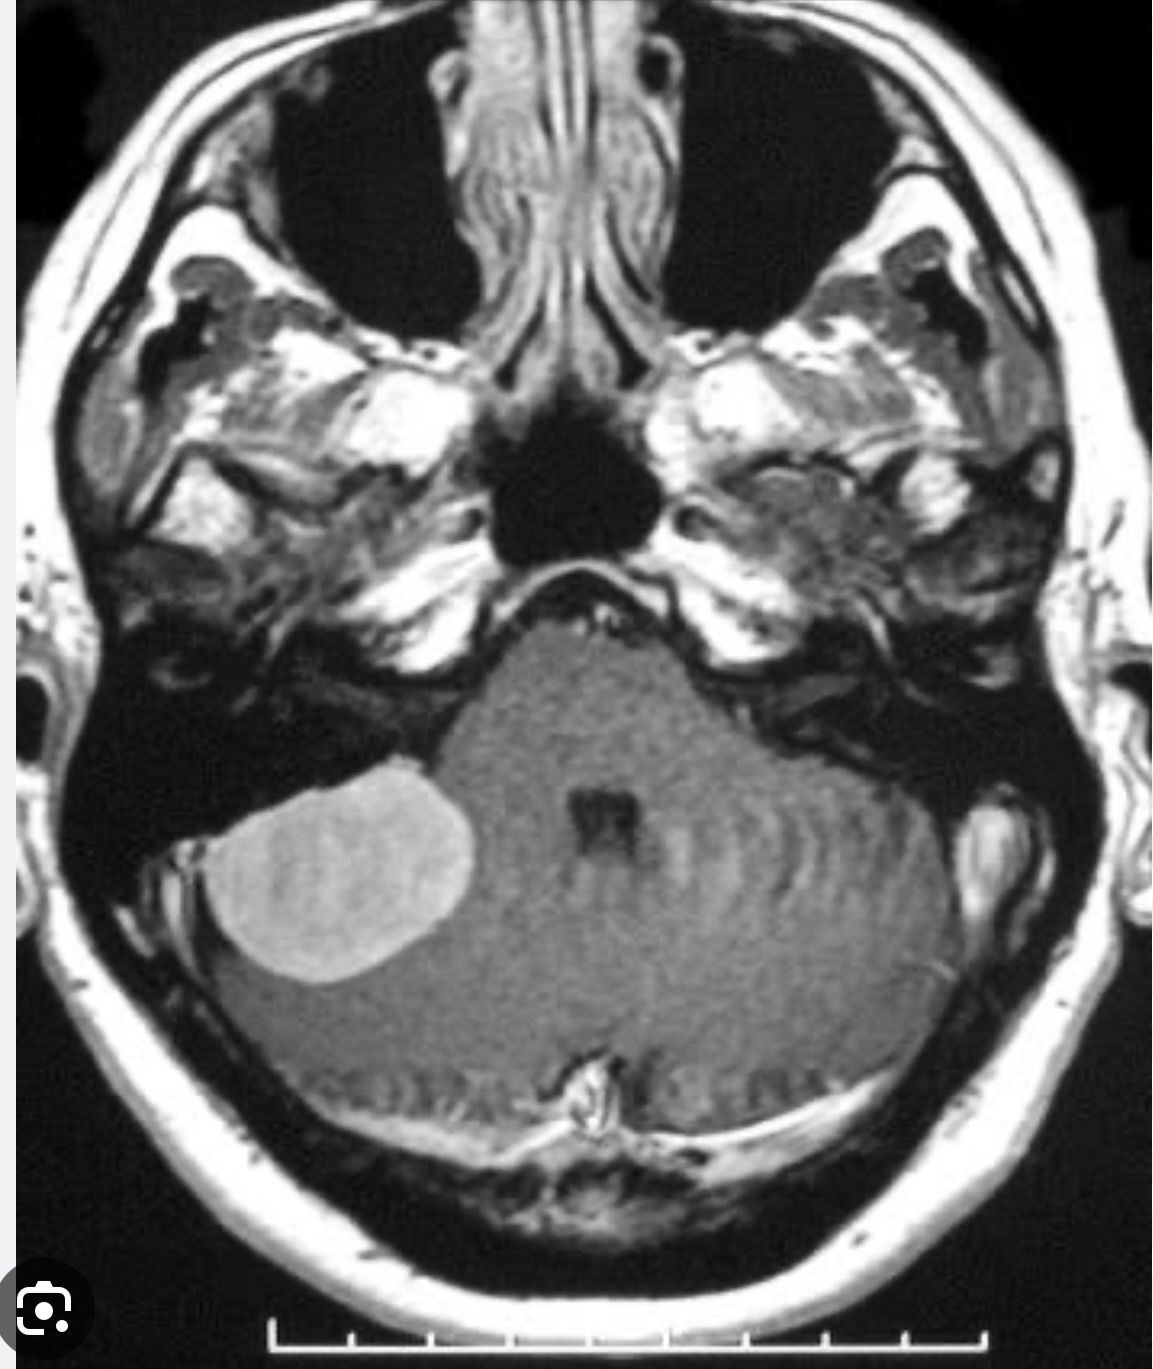

CPA tumors are mostly benign, slow-growing tumors with low potential for malignancy (~1%).The etiology of vestibular schwannoma remains unknown. However, there are two major types; Sporadic: These are unilateral tumors and most commonly present between the fourth and sixth decade of life. Those associated with neurofibromatosis (NF) type 2: The most common presentation is bilateral acoustic neuromas in younger patients with a positive family history. NF2 results from a mutation at the chromosome 22q12. This mutation leads to an increased risk of other intracranial tumors as well.